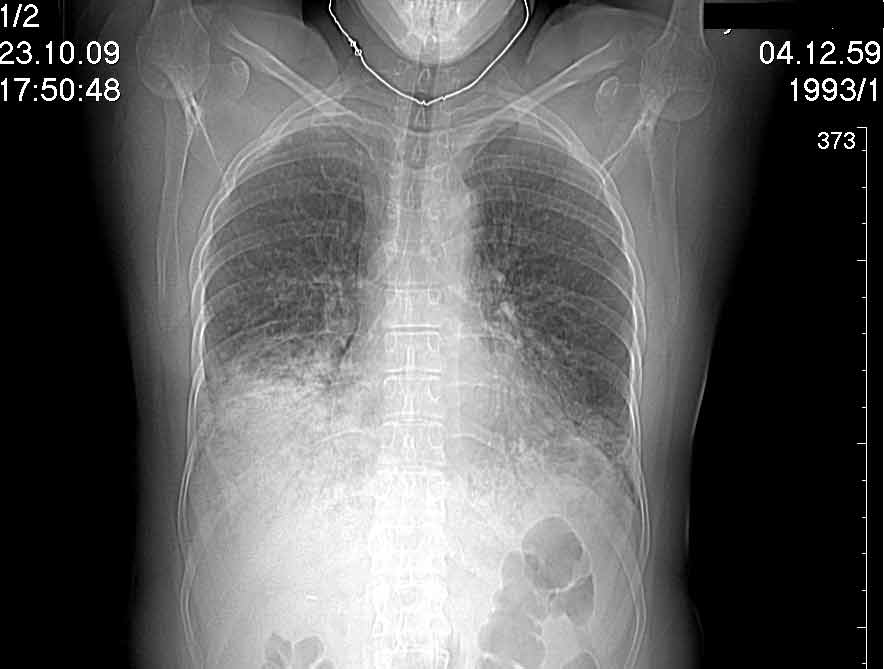

Случай №1

Женщина 50 лет.

Случай 1: изменения характерны для интерстициальной пневмонии (IIP/UIP idiopathic interstitial pneumonia/usual interstitial pneumonia); говорить о конкретной форме без открытой биопсии затруднительно.